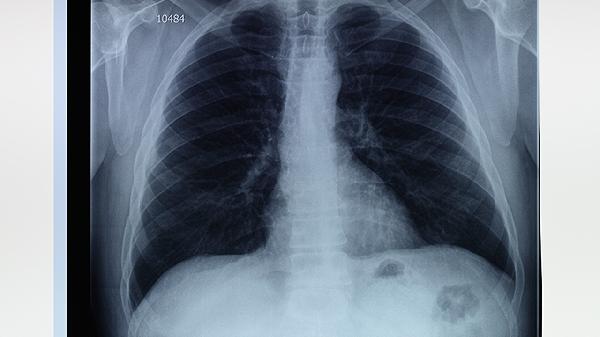

肺部切除后对生活的影响主要与切除范围、剩余肺功能及术后康复情况有关,可能出现活动耐力下降、呼吸功能受限等,但多数患者可通过科学管理维持正常生活。

肺部切除术后早期可能出现气短、咳嗽、胸痛等症状,尤其在爬楼梯、快走等体力活动时明显。这是由于肺组织减少导致气体交换面积下降,心脏负荷增加所致。术后3-6个月内,剩余肺组织会通过代偿性膨胀逐步适应,症状多可缓解。建议采用腹式呼吸训练,使用呼吸训练器帮助肺扩张,逐步恢复肺活量。饮食上需保证优质蛋白摄入,如鱼肉、鸡蛋等,促进伤口愈合。避免吸烟及接触二手烟,防止剩余肺组织进一步损伤。

全肺切除患者可能出现长期活动受限,平地行走时也可能气促。这类患者需特别注意预防呼吸道感染,秋冬季节接种流感疫苗和肺炎疫苗。睡眠时可垫高床头减少膈肌压迫,采用侧卧位避免健侧肺受压。极少数患者可能出现慢性呼吸衰竭,需长期氧疗或使用无创呼吸机辅助。术后定期复查肺功能,监测动脉血氧饱和度变化至关重要。